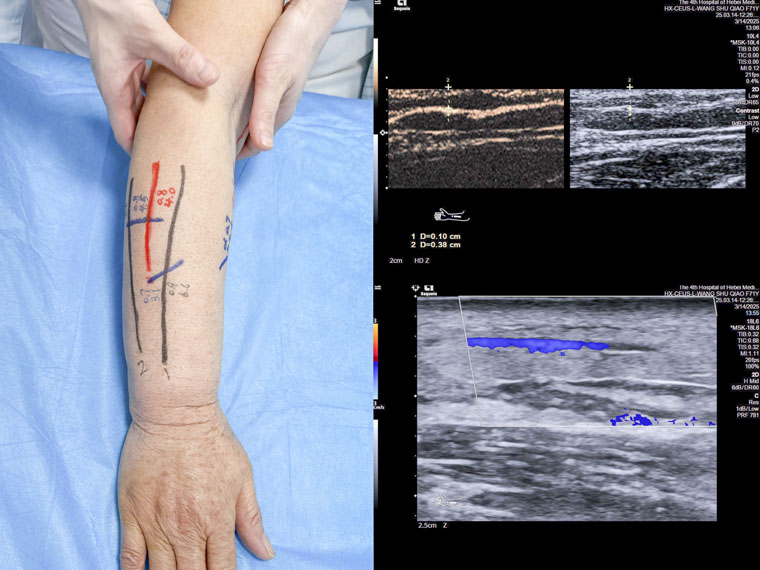

淋巴水肿患者术前定位的体表标记和超声造影的图像

在本次操作中,我院超声科殷兆麟主治医师协同科室负责人纪晓惠主任医师为一名乳腺癌术后淋巴水肿患者进行上肢淋巴管超声造影,诊断并评估淋巴管功能,精准识别有手术意义的皮下淋巴管及其邻近微静脉,并进行体表定位,助力我院乳腺中心完成河北省首例超声造影辅助下的淋巴管静脉吻合术。

淋巴水肿是一种慢性致残性和毁容性疾病,由先天性或继发性淋巴循环功能障碍引起。患者常出现上肢肿胀、疼痛和功能障碍,并可能反复感染,严重影响生活质量并造成心理创伤。淋巴管静脉吻合术是肢体淋巴水肿的一线手术治疗方案。该手术通过生理性重建淋巴通道,将淋巴管与压力较低的微静脉吻合,引流淋巴液至静脉系统内,从而减轻淋巴水肿症状。术前功能性淋巴管的精准识别定位以及理想受体静脉的选择对于缩短该手术时间、提高手术成功率至关重要。

传统的术前淋巴管定位方法为吲哚菁绿淋巴显像,但存在一定局限性,如无法显示深于1-1.5厘米的淋巴管、无法判断淋巴液流向及管壁完整性、禁用于对碘过敏的患者、不能显示用于吻合的相邻静脉等,从而导致手术耗时长,治疗效果受限。超声造影技术更容易识别淋巴管通路,优势在于可将浅层和深层淋巴管全面显示、根据造影剂流向判断淋巴管瓣膜功能情况、根据造影剂是否外溢观察淋巴管壁的完整性等。